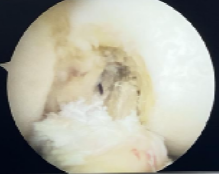

本例患者为28岁年轻女性,因意外摔伤导致左膝关节前交叉韧带完全断裂,辗转当地多家医院咨询后,最终选择前来我科手术。张智主治医师接诊患者后立即向杜恒副主任汇报,并联系尹战海主任共同讨论制定手术方案,最终确定行左膝关节镜检关节清理+半月板成形+自体腘绳肌腱重建前交叉韧带手术。

在尹战海主任的协调指导及消毒供应科的大力配合下,从总院调配关节镜设备及相关手术器械,在麻醉手术部宋珂珂、杨涵钦、李杨、高彤团队的紧密配合下,由张智主治医师主刀顺利完成手术。术后骨科任洁、孙梦媛、习姣等护理团队无缝衔接,确保了围术期无痛化管理和加速康复。术后4小时即开始无痛自主锻炼,术后1天拄拐患肢不负重活动,术后4天被动屈膝轻松达到90度,今日顺利出院继续院外康复。

2025年1月10日,我院骨科陆港院区再接再厉,单日又完成3例关节镜微创手术。分别为13岁女性外侧盘状半月板撕裂患者行半月板成形缝合修复术,为21岁男性陈旧性前交叉韧带断裂患者行自体肌腱前交叉韧带重建术,为58岁女性骨关节炎膝关节游离体患者行关节清理游离体取出术。目前这些患者均康复良好,拟于近期出院。